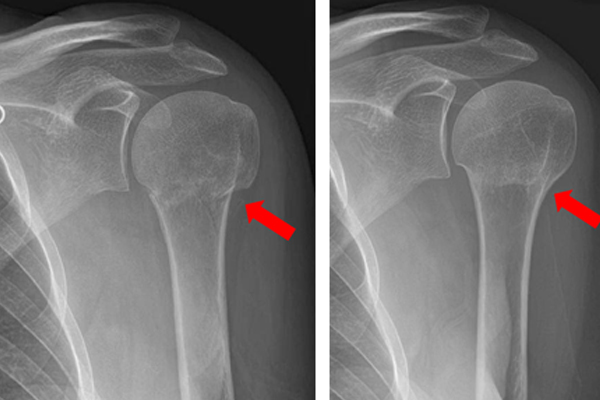

SHOULDER FRACTURES